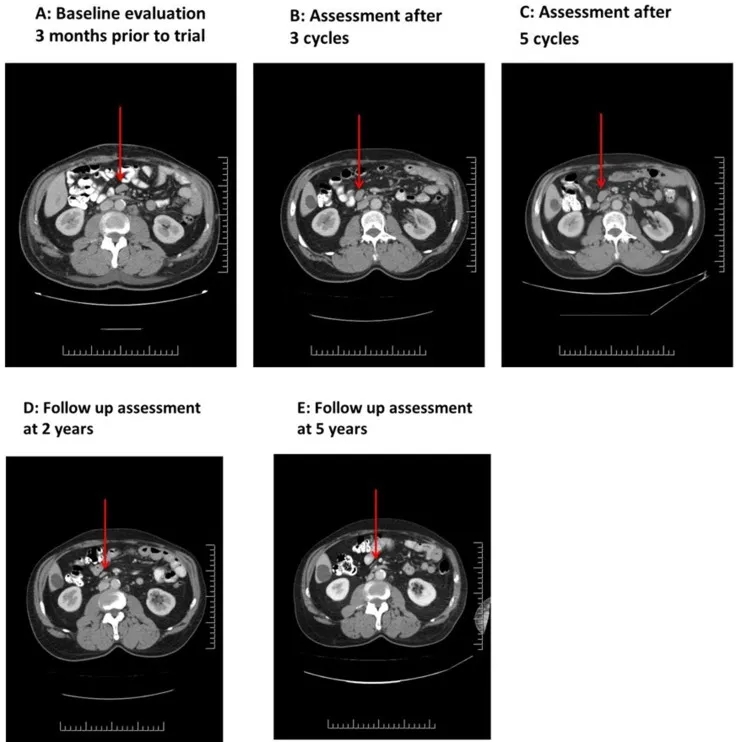

结果显示:疗效呈现明显阶段性特征:治疗前CT显示,双侧腋窝最大淋巴结长轴2.5cm,肠系膜及主动脉旁可见1cm淋巴结(详见下图A)。治疗第1周期第23天中期评估为病情稳定,最大腋窝淋巴结略有缩小;3个周期结束后,影像学显示部分淋巴结缩小(详见下图B);5个周期结束时,影像学提示淋巴结略有肿大(详见下图C),但后续24个月内所有病灶均实现缓解(详见下图D、E)。

▼此例患者(03号)在接受NK-92细胞治疗前后的连续CT扫描对比